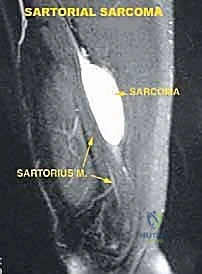

* Magnetic Resonance Imaging (MRI): Our gold standard for soft tissue evaluation. MRI precisely delineates tumor size, its invasion into neighboring structures (sartorius, vastus medialis, adductor muscles), and its proximal and distal extent into the femoral triangle or popliteal spaces. It often helps us identify the specific muscle or structure from which the tumor originates.

FIG 2 • A. Axial MR image of a tumor of the sartorial canal that arises from the muscle wall and encroaches on the vessels.